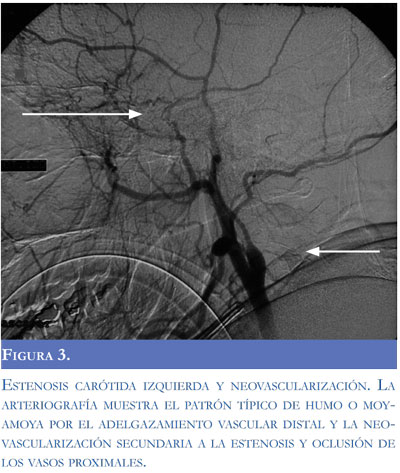

Una arteriografía realizada durante la primera semana de evolución mostró estenosis de la carótida izquierda con adelgazamiento distal de la vascula-tura cerebral con neoformación y colateralización de circulación externa con la interna conformando un patrón típico de síndrome moyamoya (Figuras 3, 4, 5 y 6). El control imagenológico hacia los 15 días de hospitalización evidenció una disminución del 50% en el volumen del sangrado intraventricular. La paciente logró llegar a un alertamiento espontáneo sin contenido de la conciencia ni respuesta al llamado. A los 45 días de evolución logra salir de UCIN con traqueostomía percutánea y nutrición por gastrostomía.

El termino moyamoya fue introducido por Suzuki y Takaku en 1957 por el aspecto angiográ-fico de la circulación colateral cerebral en humo de cigarrillo o fumarola (en japonés "moyamoya"). En esta entidad existe una esteno-oclusión de múltiples vasos intracraneales con aparición de colaterales del polígono de Willis, leptomeningeas o con formación de aneurismas u otras malformaciones arteriovenosas. Cuando existen colaterales entre circulación anterior y posterior o entre la circulación intracraneana y la extracraneana existe mayor riesgo de hemorragia intracraneana. En la enfermedad de moyamoya existe predisposición genética, en cambio, en aquellos pacientes sin la enfermedad pero con el patrón angiográfico típico existe una enfermedad de base (síndrome de moyamoya) que los predispone a desarrollar el daño vascular, como la ateroesclero-sis en ancianos, la neurofibromatosis, la esclerosis tuberosa, la tuberculosis, el síndrome de Down y la enfermedad de células falciformes (5-6). Dobson describió 44 pacientes con enfermedad de células falciformes y demostró que aquellos con síndrome o patrón angiográfico de moyamoya tuvieron más riesgo de eventos cerebrovasculares recurrentes (7).